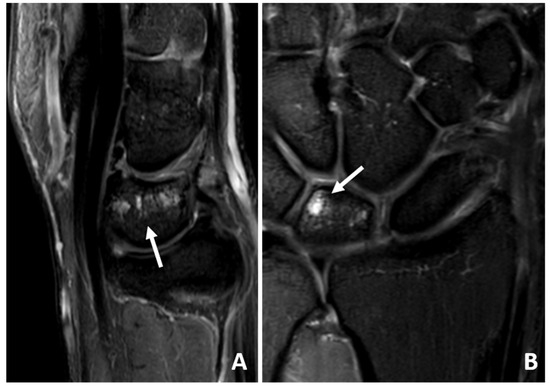

2.5. Magnet Resonance Imaging

3.4. MRI Scan